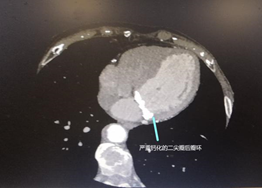

2019年10月的某一天,杨秀滨主任办公室来了一位七十多岁的老年女性重度二尖瓣关闭不全患者,希望杨主任能够帮助她来做二尖瓣置换手术。这之前患者已经到访过几家大医院,但没有人愿意接诊这例患者。这是一例什么样的二尖瓣关闭不全患者,病情很特殊吗?原来患者不仅多年前做过左侧乳腺癌根治手术和局部放疗术治疗,而且还有严重的冠心病,需要搭3-4根桥,更重要的是患者的二尖瓣后瓣环严重钙化,无法进行常规的换瓣手术!

超声心动图是最主要的诊断方式。此外,CT和MRI也可对其进行诊断。特别严重的钙化,通过胸片亦可诊断。